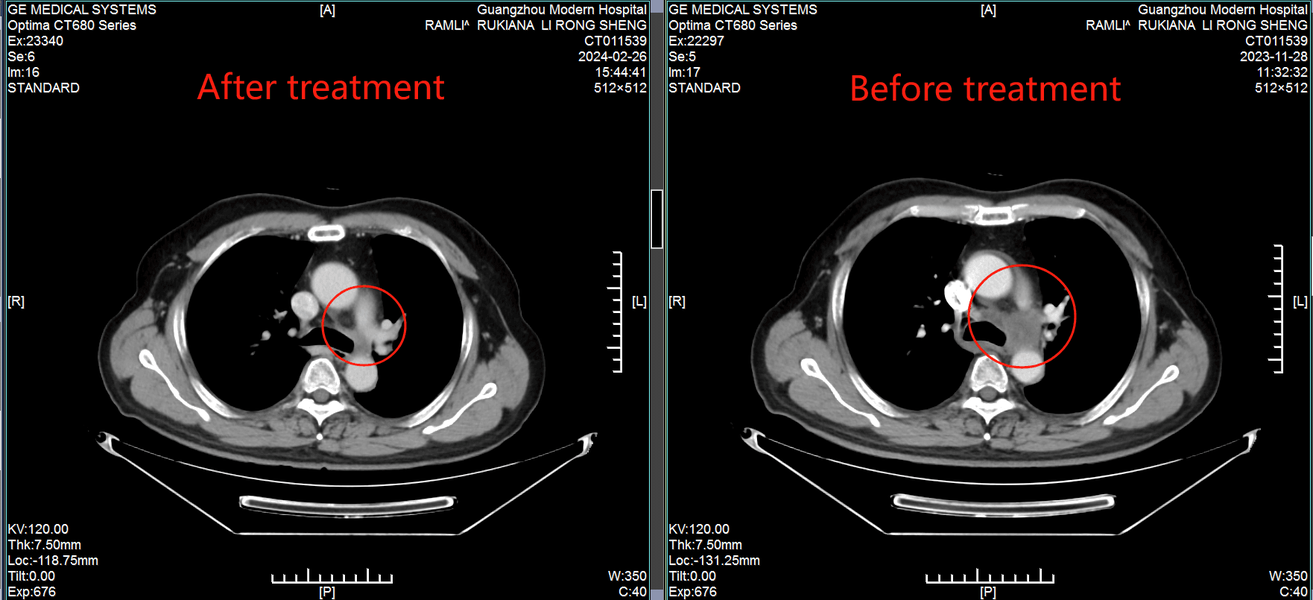

История надежды: Рамли Рукиана из Индонезии побеждает рак легких IV стадии при серьезных сердечных заболеваниях

50-летний пациент с функцией сердца 30% достиг ремиссии благодаря щадящим технологиям в Гуанчжоу

В ноябре 2023 года у Рамли Рукианы из Батама (Индонезия) появилась необъяснимая охриплость голоса. Обследование в Сингапуре выявило шокирующую правду: рак левого легкого IV стадии с метастазами в лимфоузлы. Опухоль размером 1.7 см усугублялась критическим состоянием сердца - функция составляла всего 30%. Местные врачи не предлагали вариантов, кроме рискованной операции. «Я думал, это конец. Боялся рассказывать семье и готовился к худшему», - вспоминает Рамли.

• Через 2 месяца: Опухоль в легком практически исчезла, метастазы в лимфоузлах значительно уменьшились. • Сердечная функция стабилизировалась - лечение не усугубило риски. • Возврат к активной жизни: Рамли общается с пациентами из других стран, используя переводчик, и вдохновляет их своим примером.

КТ-снимки подтвердили: динамика положительная, болезнь отступает

26 февраля 2024 года результаты КТ показали, что опухоль легкого значительно уменьшилась